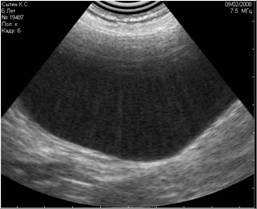

- вызванные недостаточным количеством УЗИ-геля, нанесённого на кожу (Рис.4) ;

Рис 4. Недостаточное количество геля при проведении УЗИ (правая половина снимка). |